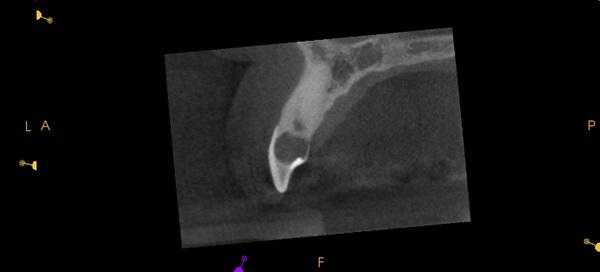

Фото 9. Подтверждение диагноза на КТ-срезе.

Фото 10. Распространение ИПКТ в парапульпарном апикальном направлении (срез КЛКТ).

По причине принципов получения рентгенологических изображений, двухмерной природы рентгенограмм и значительного перекрытия нескольких анатомических образований, периапикальные снимки, или снимки по типу bitewing, часто не являются достаточно чувствительными для диагностики ИПКР. Также информативность данных методов при ИПКР часто связана с объемом потери твердых тканей зуба. Конусно-лучевая компьютерная томография (CBCT) является особенно полезной на ранних этапах регистрации очага поражения, хотя учитывая, что данный метод редко используется с целью скрининга, ИПКР снова-таки часто диагностируется как дополнительная находка при диагностике каких-то других заболеваний или при планировании комплексных алгоритмов лечения. Пародонтальная потеря костной ткани крайне редко отмечается в области внешней пришеечной резорбции.

При рентгенологической идентификации ИПКР чаще всего напоминает кариозный дефект V класса. При локализации поражений со щечной или язычной сторон из-за графического наложения на область пульпы зуба они могут вызывать некую размытость ее контура. По мере развития патологии она прогрессируют к пульповой камере, не вызывая прямого воздействия на пульпу. В большинстве случаев, даже среди обширных поражений, твердые ткани, окружающие пульпу, часто выглядят почти неповрежденными, что на рентгенограмме проявляется в форме тонкой рентгеноконтрастной линии между дефектом ИПКР и пульпой зуба.

На КЛКТ внешняя резорбция проявляется как неравномерная рентгенопрозрачность и интактный канал зуба, внутренняя же резорбция выглядит как четкий очаг без прослеживания корневого канала.

КЛКТ с успехом применяется для определения внутренней резорбции и дифференциации ее от внешней. Обычная рентгенография часто не может выявить верный объем распространения, локализации и источник резорбтивного процесса. КЛКТ помогает в определении с тактикой лечения, а также предлагает составить верный прогноз на основе активности и распространенности поражения. И лечение, и результат лечения таким образом становятся более предсказуемыми.